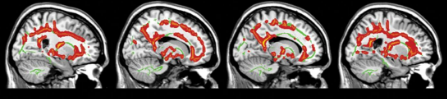

Degeneración cortico-basal (CDB)

Conlleva principalmente síntomas motores y cognitivos. Los síntomas motores suelen afectar un brazo y/o una mano, incluyendo: lentitud, rigidez, mioclonías, que son sacudidas rápidas de los músculos y distonía, que es una postura fija y anormal.